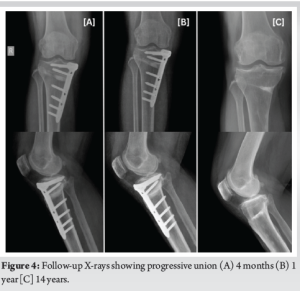

A 56-year-old female was diagnosed with medial compartment osteoarthritis (Kellgren-Lawrence grade 3) with varus malalignment (Fig. 1a) and medial meniscus posterior root tear. The patient was planned for arthroscopic medial meniscus root repair and MOW-HTO. The planned correction angle was 8.5° with opening wedge thickness of 9 mm (Fig. 1c). Meniscus root was repaired with a suture anchor. For the osteotomy, a small vertical incision was taken over the medial aspect of the proximal tibia below the joint line and midway between anterior and posteromedial margins of tibia. The pes anserinus tendon was identified and superficial medial collateral ligament (sMCL) partially released at that level. A radiolucent Hohmann retractor was strategically placed from under the released sMCL going posteromedial to protect the neurovascular structures. The Hohmann was placed obliquely all the way along the osteotomy line which was directing toward the tip of fibula under fluoroscopy guidance (Fig. 2). Osteotomy path was positioned using 2 K-wires starting just above pes anserinus level at the medial metaphyseal flare of tibia aiming toward the tip of fibula. Once sure, osteotomy was done was oscillating saw and opened using “3 chisel technique.” The correction was planned using Miniaci technique at Fujisawa point, i.e., 62% of tibial plateau as measured from medial side (Fig. 1b). Care was taken to maintain the lateral hinge. The open wedge was filled with tricalcium phosphate (TCP) bone substitute toward the cortex to prevent post-operative collapse and loss of correction. Osteotomy site was secured with locking TOMOFIX plate. Drilling for screws was done carefully not to cross far beyond the distal cortex. The TCP and the plate were purposely kept postero-medially and fixed in knee extension to maintain the posterior tibial slope angle. The procedure was uneventful. On post-operative day 1, the patient complained of decreased sensation over the posterolateral area of leg and sole of foot along with generalized tingling in the lower limb with inability to flex the great toe (Video 1a). Rest of the neurovascular examination was normal. Post-operative X-rays showed good fixation with no protruding hardware. Magnetic resonance imaging of lumbosacral spine was done which showed mild disc bulge at L4-L5 and L5-S1 with no nerve compression or canal stenosis. This could not be related to patient’s symptoms. Nerve conduction velocity (NCV) test was done at 3 weeks which showed right tibial nerve injury pattern around knee level with moderate axonotmesis (Fig. 3a). Since the nerve was in axonotmesis, a conservative trial with a close follow-up was planned for the patient. The patient was given electrical stimulation therapy, interferential current therapy, physiotherapy, and pregabalin course. On 2-month follow-up, there was no pain. The patient was mobilizing full weight bearing. However, there was no neural recovery clinically. On 4-month and 1-year follow-up, great toe flexion power was 2/5 and there was a 50% subjective improvement in sensory complaints. The X-rays showed good progressive union (Fig. 4). Unfortunately, after this, the patient was lost to follow-up and came back to us after 5 years (6-year post-surgery). The patient had the osteotomy plate removed at another hospital. At this time, the patient had persistent paresthesia (subjectively around 40%) and great toe flexion was 4/5. The last follow-up is 14-year post-surgery where the motor function has recovered completely with some residual paresthesia (Video 1b).

However, the patient complained of discomfort after walking for long distances. The NCV at this stage was suggestive of chronic tibial nerve injury (Fig. 3b). Long leg X-ray showed some loss of correction with axis passing through 50% point (Fig. 1e), but the patient had no arthritis-related complaints.